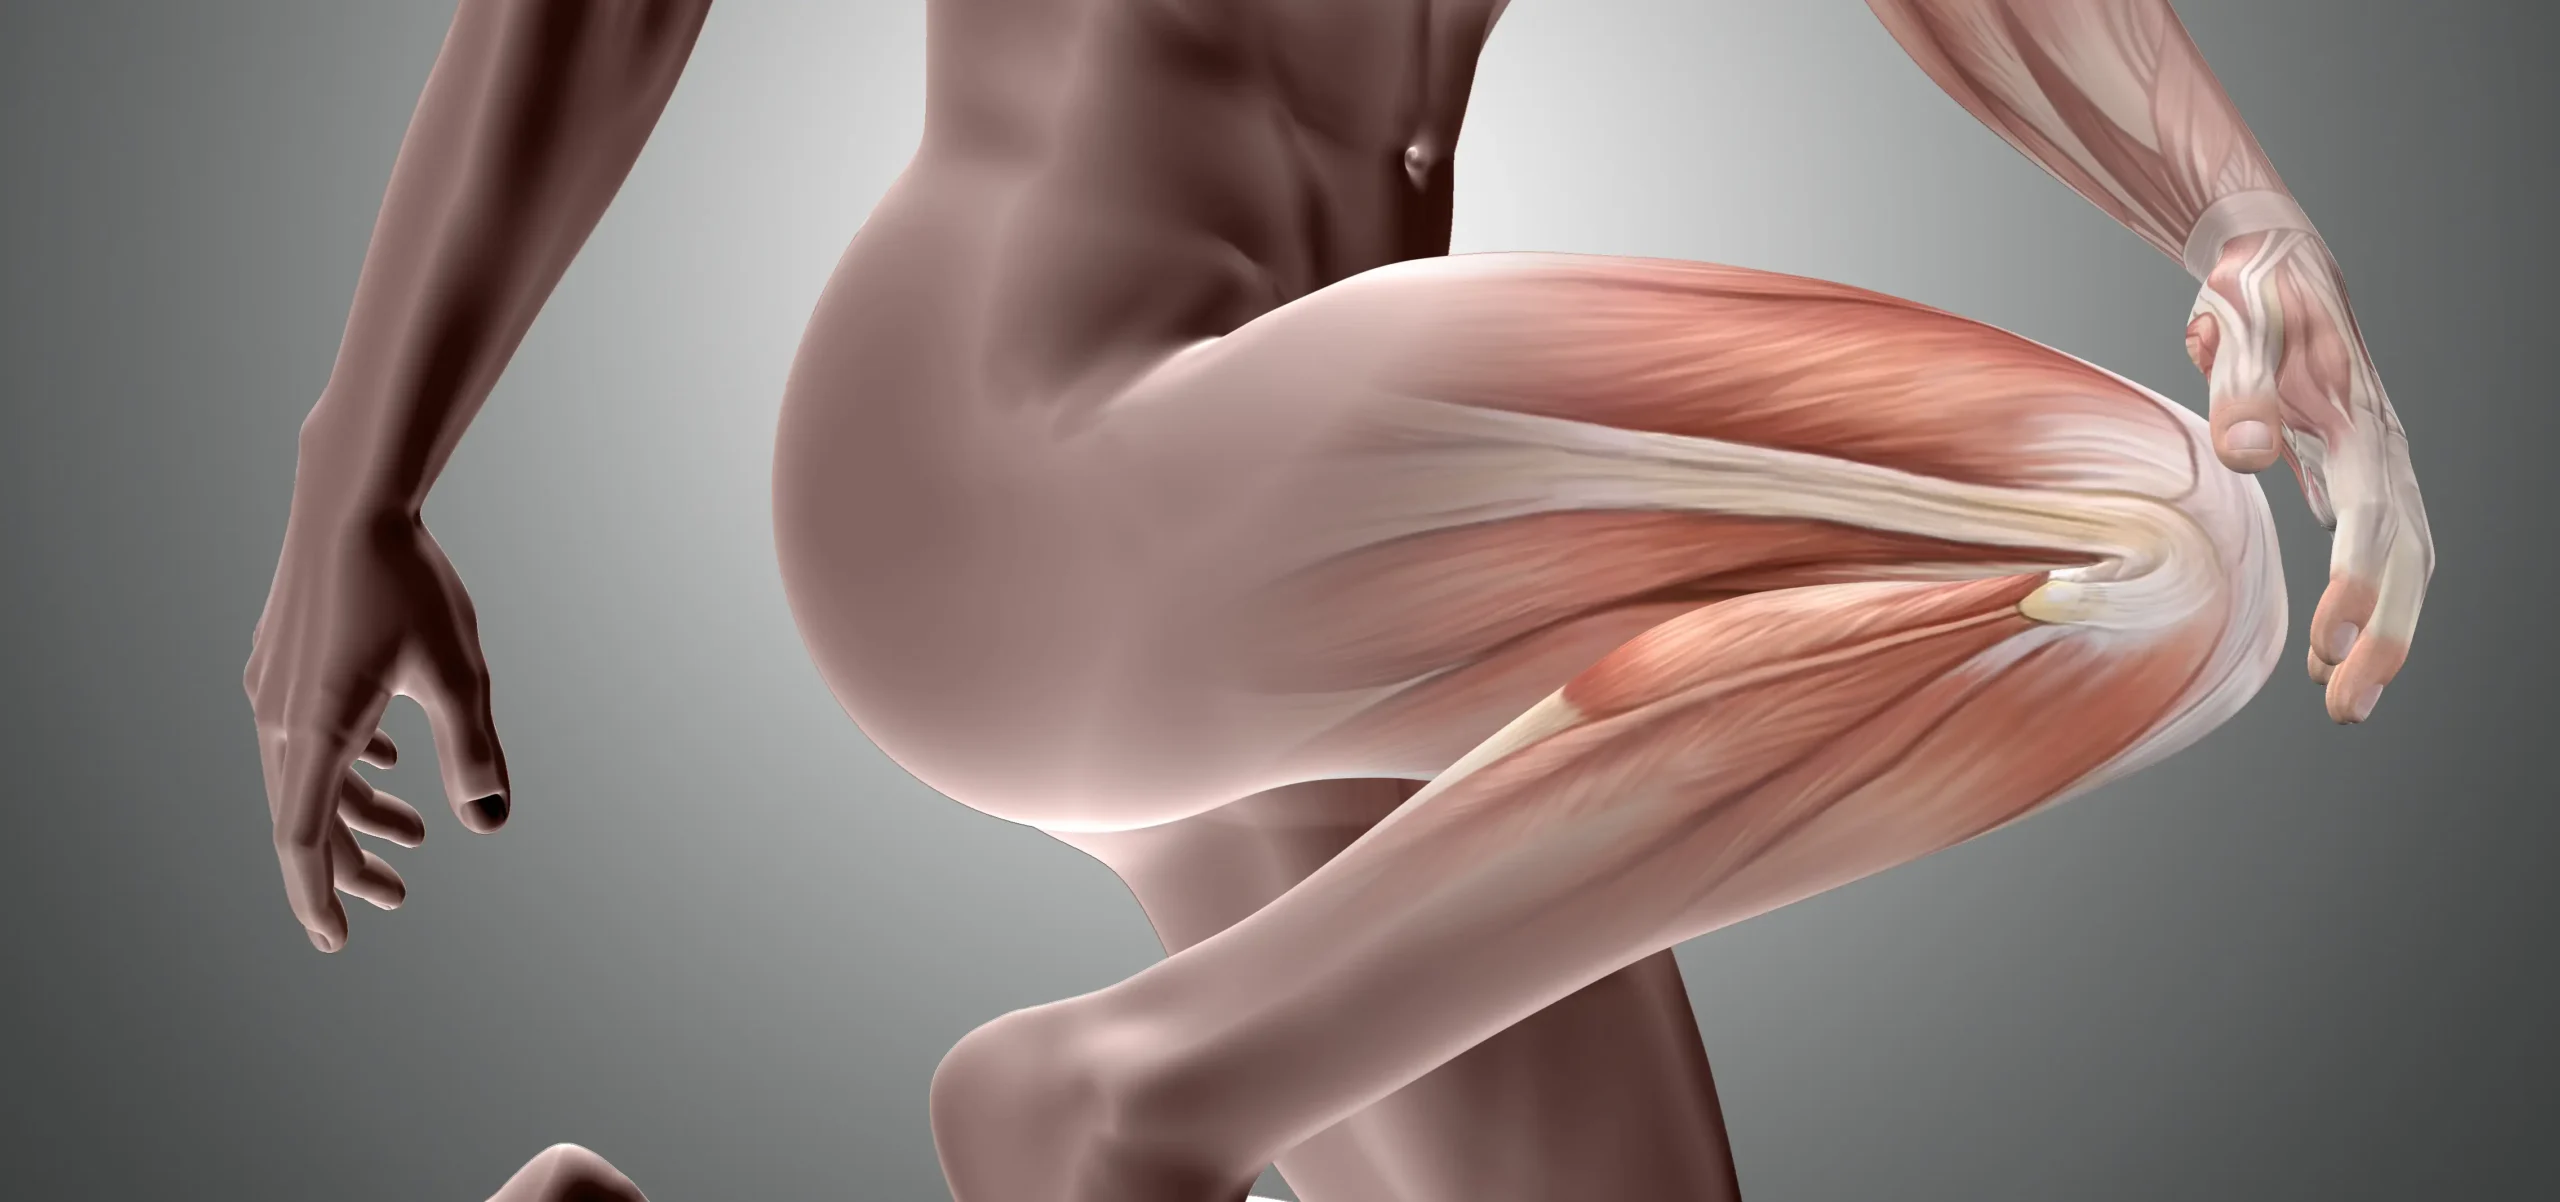

Bacaktan Vuran Ağrı: Siyatik Sinir Sıkışması

Bacaktan Vuran Ağrı: Siyatik Sinir Sıkışması